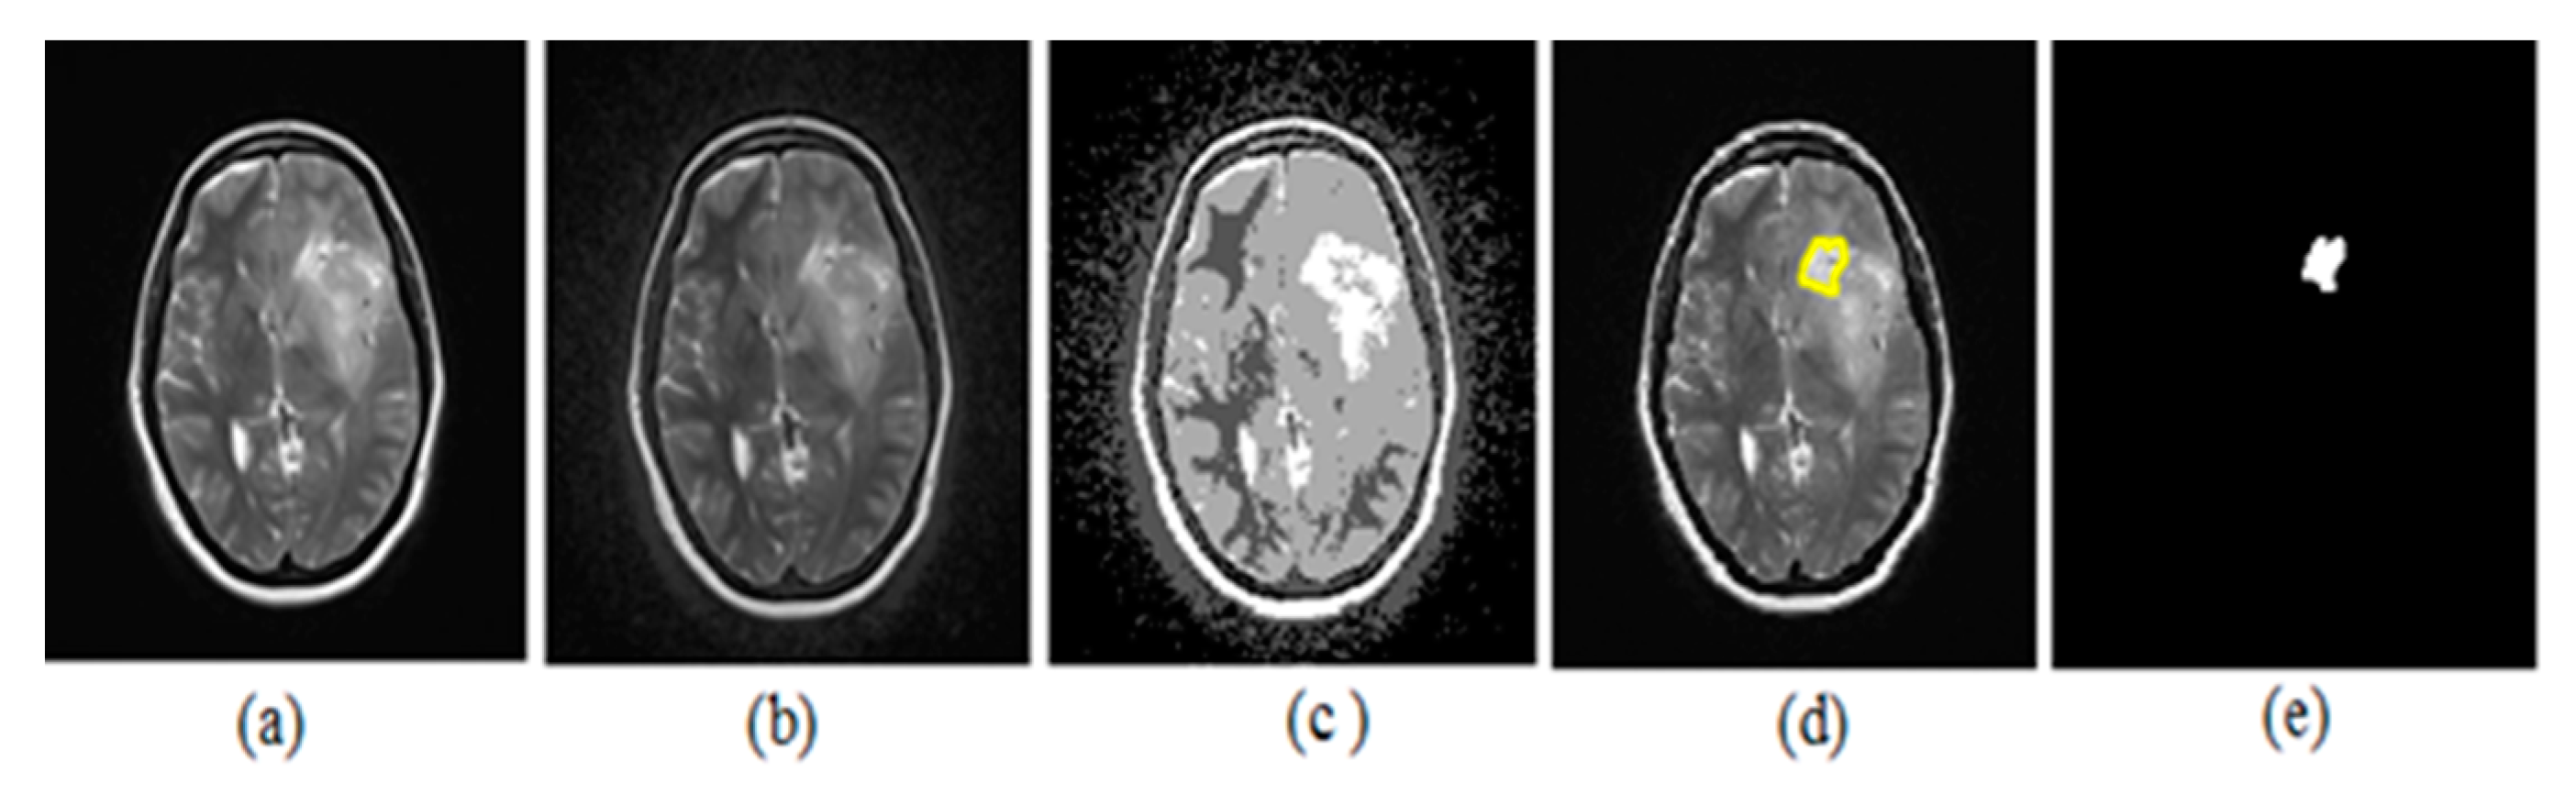

The upcoming figures are sectioned into three parts: Each part has an original neonatal brain image, and segmentation is achieved on that image. All the sections were subdivided into two parts—a and b. Part ‘a’ helps in visualizing tumor detection over the original image (which is not enhanced). On the other hand, part ‘b’ is of the enhanced image. Figure 10 represents the (a) original image, (b) preprocessed with BPDFHE enhanced image, (c) segmentation result using the median filter, (d) detection of the tumor, and (e) extraction of the tumor using thresholding.

Figure 10.

(a) Original image, (b) BPDFHE enhanced image, (c) segmentation result using median filter, (d) detection of tumor, and (e) extraction of tumor using thresholding.

The estimation of the proposed hybrid method for preprocessing and segmentation using a machine learning algorithm was shown on various MRI images to detect tumors. We placed the images for better visibility after simulations in ink space were used.

Justification of the results was carried out with the dice index (DI) and Jaccard index (JI). The ground truth (GT) image was considered to estimate the performance, which was prepared with the help of a radiologist.